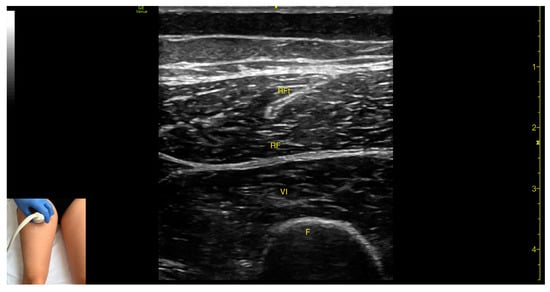

3.4. Rectus Femoris (RF)

3.4.1. Overview

3.4.2. Ultrasound Identification

3.4.3. Key Ultrasound Landmarks

- Muscle morphology: The RF is a bipennate muscle, characterized by a central septum, with muscle fibers attached on both sides and continuing into a central tendon. These two fiber regions should be individually targeted during injection

- Muscle position: It is the most superficial muscle mass at this level. Lateral to the rectus femoris lies the vastus lateralis, and medial to it, the vastus medialis.

- External fascia: A pronounced fascia separates the rectus femoris from the subcutaneous plane and adjacent muscles: vastus intermedius, vastus lateralis, and vastus medialis.

- Dynamic evaluation: During dynamic evaluation, scanning distally toward the knee joint, the muscle bulk of the RF decreases, but its central tendon remains visible until the distal third of the thigh (Video S1). Muscle contraction is visible during hip flexion and knee extension maneuvers.

3.4.4. Clinical Implications and Injection Strategy